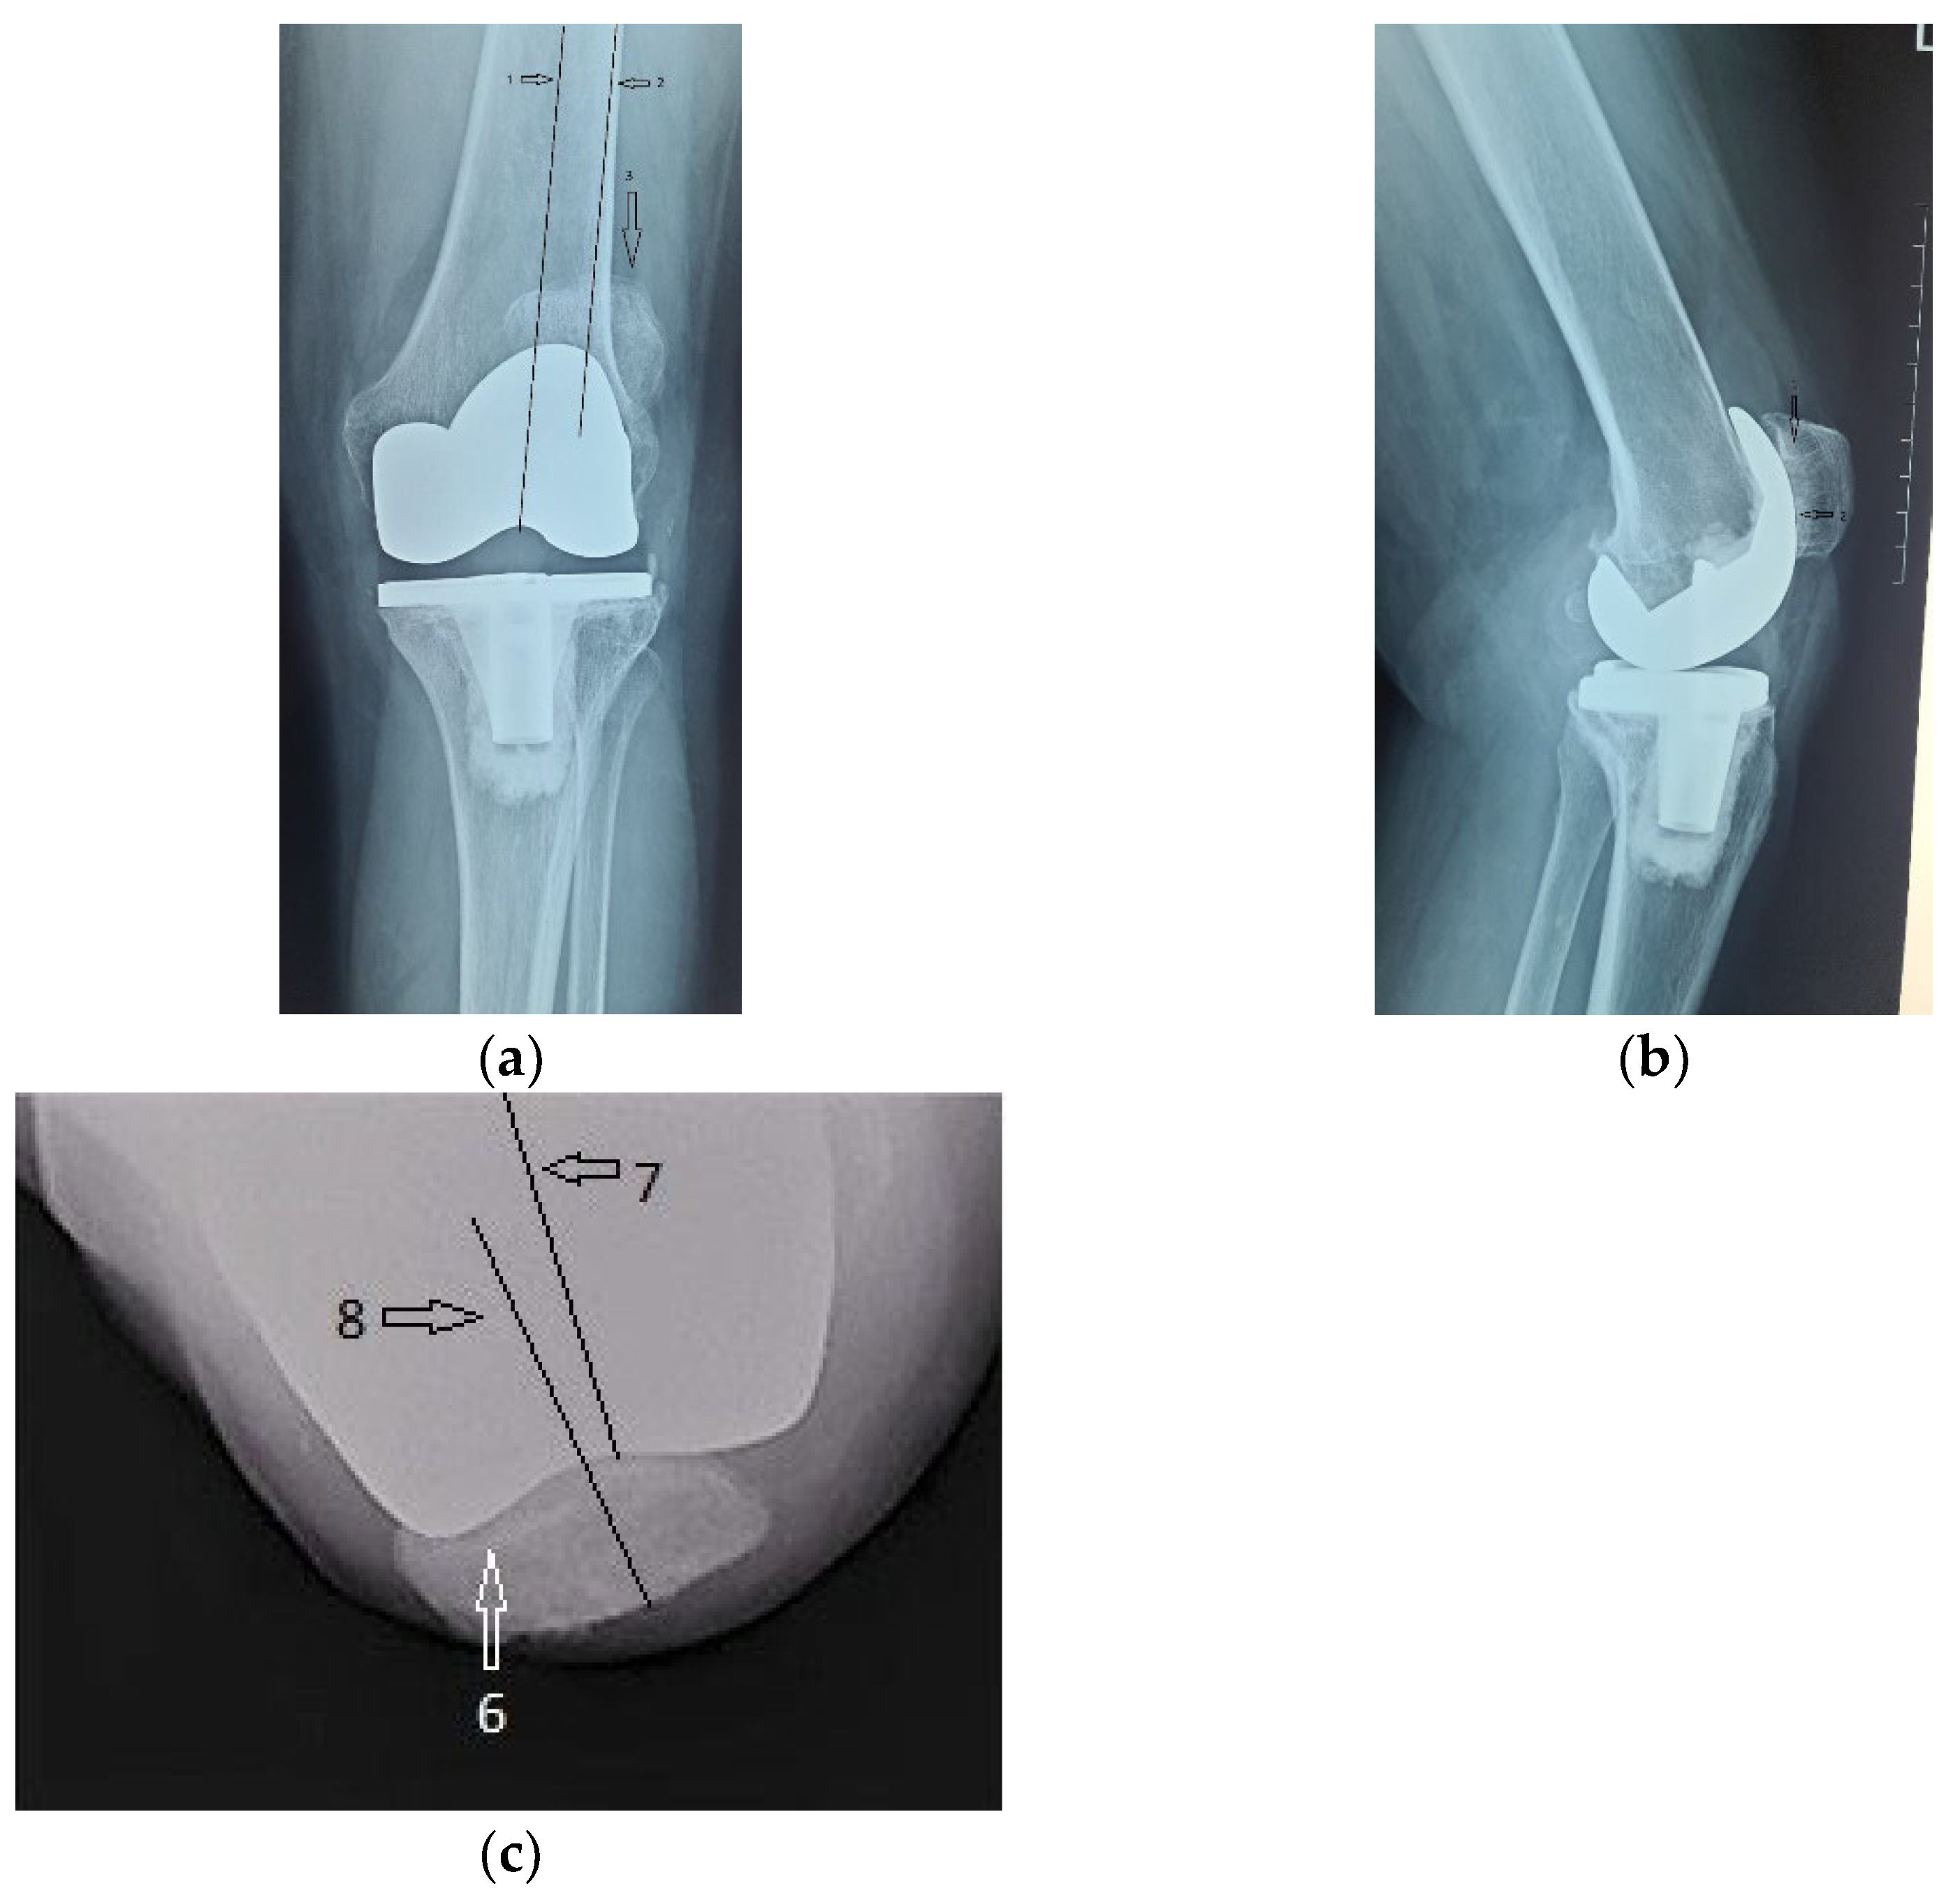

The immediate and distant postoperative evolution were favorable, as the radiological evaluation performed on the 2nd day after surgery shows; unfortunately, the lateral view is rotated (Figure 6).

Figure 6.

(a) Coronal view, patella centered on femoral axis (arrow); (b) Lateral view.

Radiological and clinical follow-up were performed at 6 weeks, 3 months and then 12 months after surgery (Figure 7, Figure 8 and Figure 9).

Figure 7.

Radiological imaging at 6 weeks after surgery: (a) Coronal view; (b) Lateral view.

Figure 8.

Radiological imaging at 3 months after surgery. (a) Coronal view, patella is centered to the femoral component (arrow); (b) lateral view.

Figure 9.

12 months after surgery: (a) coronal view, normal centered patella; (b) lateral view, no signs of patellar loosening; (c) axial view, normal centered patella in femoral trochlea.